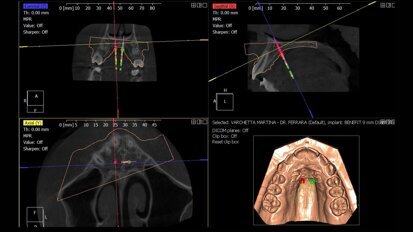

Digital Sinus Planning (DSP) Protocol: Protocollo digitale per programmare una rigenerazione ossea verticale/orizzontale

Introduzione L’elevazione del seno mascellare con approccio laterale è una tecnica chirurgica con molta evidenza nella letteratura scientifica ...